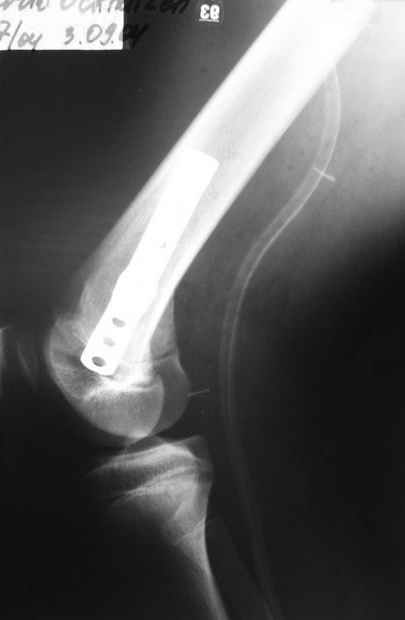

Как вариант решения прогрессирующей вальгусной деформации коленного сустава я бы предложил косую остеотомию дистального отдела бедра с фиксацией пластиной и компрессирующим винтом.

Взгляните на снимки , может быть это вам поможет.

Около 5 лет применяю этот тип дистальной остеотомии бедра для коррекции механической оси Н/К ( более 20 случаев) - достаточно эффективная операция.

- Конечно, другая: я применял этот тип остеотомии при различных состояниях, приводящих к деформации механической оси сустава, но техника её тандартна,

расчеты индивидуальные.

-Деформация оси сустава может быть варусной или вальгусной, причины - структурные изменения в латеральном -или медиальном отделе сустава (переломы, патология зон роста, дисплазии, дегенеративные процессы) результат лечения внутри- или внесуставного перелома и восстановление оси обуславливается анатомичностью репозиции и адекватностью фиксации. Нередко в запущенных -неправильно срасшихся unicompartmental внутрисуставных переломах восстановление оси и опороспособности достигается периартикулярными

остеотомиями...